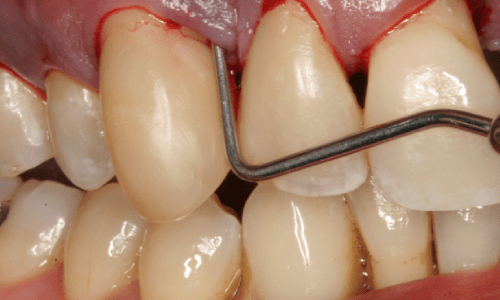

• A small flap incision is made, and the gums are gently separated from the teeth.

• The dentist gains direct access to the roots and jawbone.